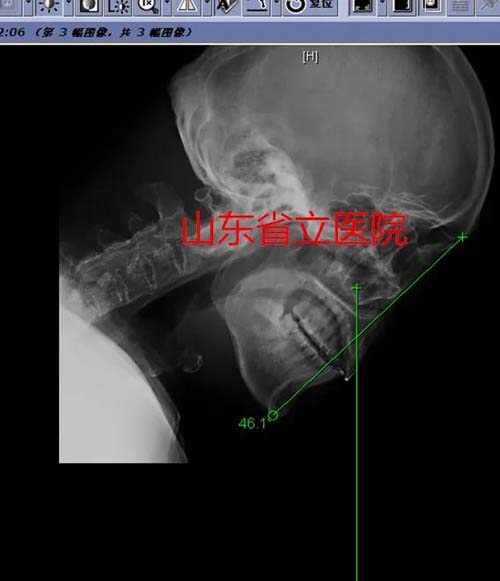

今年54岁的姬先生患强直性脊柱炎多年,他的脊柱渐渐“石化”,尤其是随着病情逐步加重,头部已日益低垂,不能正常抬起,46.1度的颌眉角使他成了一个“颌触胸”的“低头人”,如果想平视或与人交谈,就只能屈膝屈髋,使整个身体呈半蹲状态。行走、平躺睡觉、仰头喝水……这些正常人日常生活中轻而易举做到的动作,姬先生却可望而不可及。半个多月前,一场意外导致的颈椎骨折,使他处于随时可能高位截瘫,甚至危及生命的高度危险状态,慕名到省立医院就诊,开启了他实现“抬头”愿望的第一步。

手术矫形24度,颌眉角由术前的46.1°矫形到术后的22.3°,很好的解决了患者不能抬头的问题,使患者的生活质量得到极大改善。经数月休养后,患者的社会生活和交往必将会极大改善。